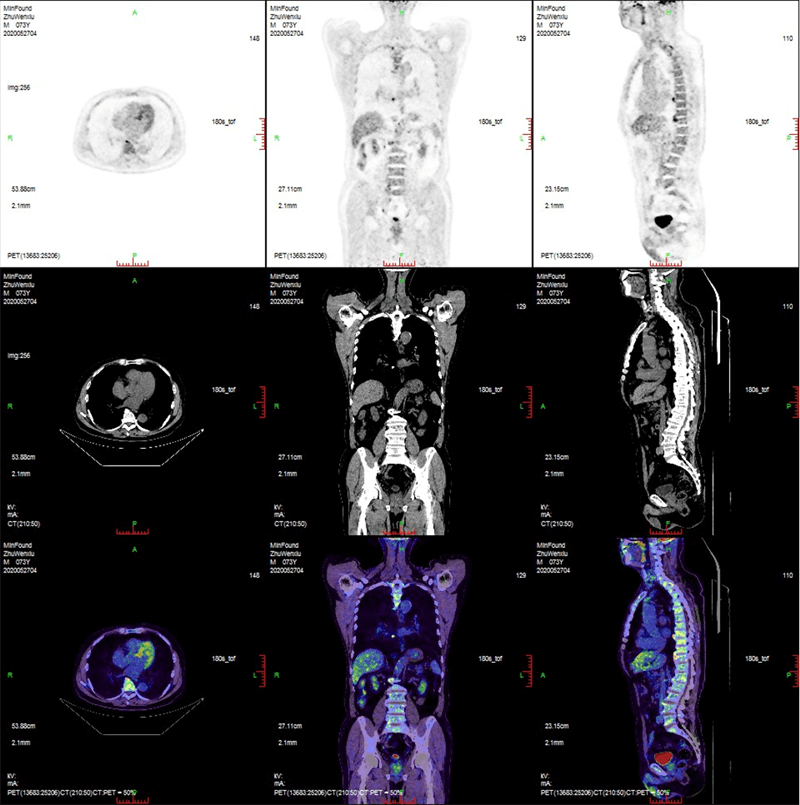

ScintCare PET/CT 720E

ScintCare PET/CT 720E uses the 4th-generation PET detector with which lutetium-yttrium oxyorthosilicate (LYSO) crystals are individually coupled to SiPM detectors without the optical conductor. This digital SiPM-based detector ensures 100% crystal coverage to the SiPM and greatly improves photons efficiency and images quality.

The 20.16 cm axial FOV compare to the conventional 16 cm axial FOV PET/CT, it speeds up the scanning process allowing greater patient throughput.

臨床畫廊